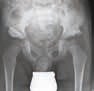

Bei jüngeren Kindern mit Zerebralparese oder Kindern mit leichterer Form einer Subluxation des Hüftgelenks kann ein reiner Weichteileingriff in Form einer Adduktorentenotomie ausreichend sein, um das Muskelungleichgewicht zu beseitigen. Es kommt dabei zu einer Normalisierung der weiteren Hüftentwicklung. Bei manchen Kindern zeigt sich jedoch ein Rezidiv mit Überwiegen der Adduktoren. In diesen Fällen kommt es über die Entwicklung einer Coxa valga zu einer Progredienz der neurogenen Hüftdysplasie und einer zunehmenden Lateralisierung des Femurkopfes bis hin zur Luxation. Bei diesen Kindern ist eine intertrochantäre derotierende varisierende Osteotomie und bei ausgeprägter Pfannendysplasie eine zusätzliche Beckenosteotomie erforderlich. Um postoperativ einem erneuten Überwiegen der Adduktoren entgegenzuwirken, sollte eine Lagerung in einer nach Maß angefertigten Ganzkörper-Abduktionslagerungsschale erfolgen (Abb. 11).